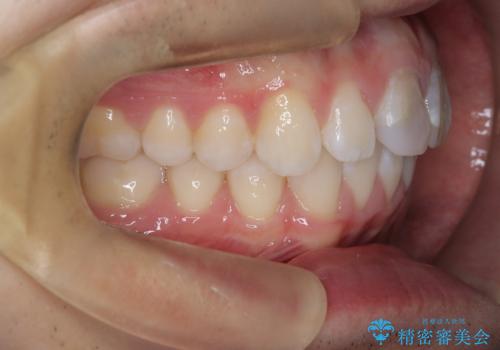

【ワイヤー矯正 11ヵ月で矯正終了!】歯のでこぼこを治したい!

- 「歯のでこぼこを治したい 1年くらいで矯正を終わらせたい」を主訴に来院された患者様です。

叢生量は多く無く歯の傾斜も標準傾斜だったので歯は抜かずにワイヤー矯正で治療を行いました。

左側は2級傾向が強く臼歯の遠心移動をご提案しましたが、1年以内に矯正を終わらせたいという患者様のご意向で希望されず叢生を改善する矯正となりました。